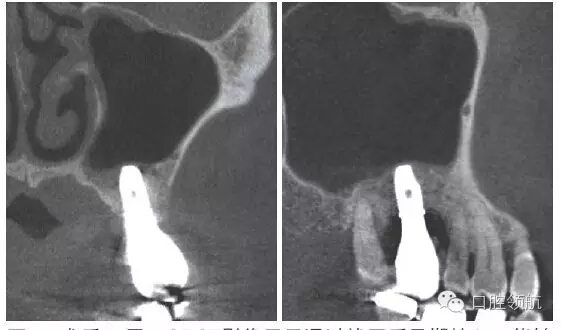

患者,78歲,男性 ,因6 牙齦腫脹來院,檢查見牙根周圍因牙槽骨缺損表現(xiàn)為透過影像(圖1)。在制訂治療計劃時,對于因重度牙周炎、慢性根尖周炎、牙根折斷等原因?qū)е碌难例X缺失需要行上頜竇底提升術(shù)的病例,不能單純考慮缺牙區(qū),要同時考慮鄰牙狀態(tài),并用CBCT確認(rèn)上頜竇底黏膜是否有增厚,這是非常重要的。該病例,根據(jù)CBCT能夠觀察到上頜竇底黏膜增厚,拔牙即刻植入感染幾率較高。計劃拔牙后4~8周,拔牙窩牙齦上皮愈合但拔牙窩未消失時(拔牙后早期植入)植入種植體(圖2)。

圖1 CBCT影像確認(rèn)是由6 引起的上頜竇底黏膜增厚。